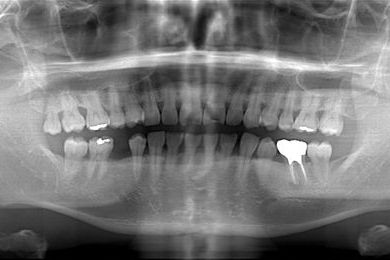

| 性別/年齢 | 男性 / 37歳 | ||||||||||||||||||||||||||||||||

| 治療方針 | 右下欠損部分をインプラント治療にて、機能的・審美的回復を行う。 | ||||||||||||||||||||||||||||||||

| 治療内容 | インプラント1本、メタルボンドセラミッククラウン1本 | ||||||||||||||||||||||||||||||||

| 総治療費 | 252,000円 | ||||||||||||||||||||||||||||||||

| 治療期間 | 7ヶ月 |